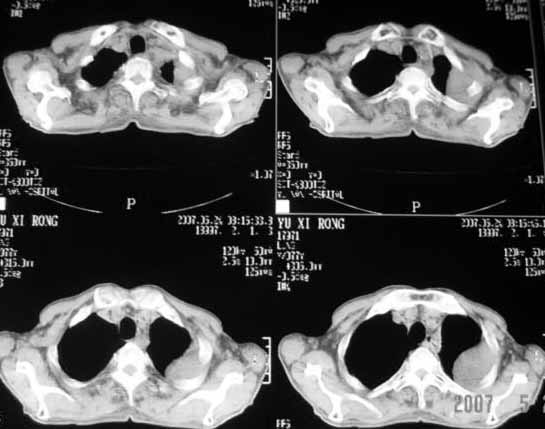

以下是引用luochengyi在2007-5-24 14:33:00的发言:[br]考虑左下肺癌。左侧胸腔积液。

以下是引用adams在2007-5-24 17:12:00的发言:[br]支持“考虑左下肺癌,左侧胸腔积液,建议胸水检查”。[br] [br]

以下是引用fumaogui在2007-5-24 16:20:00的发言:[br]左侧胸腔积液.[br]左下叶不张考虑中心型肺癌[br]建议纤支镜检查.